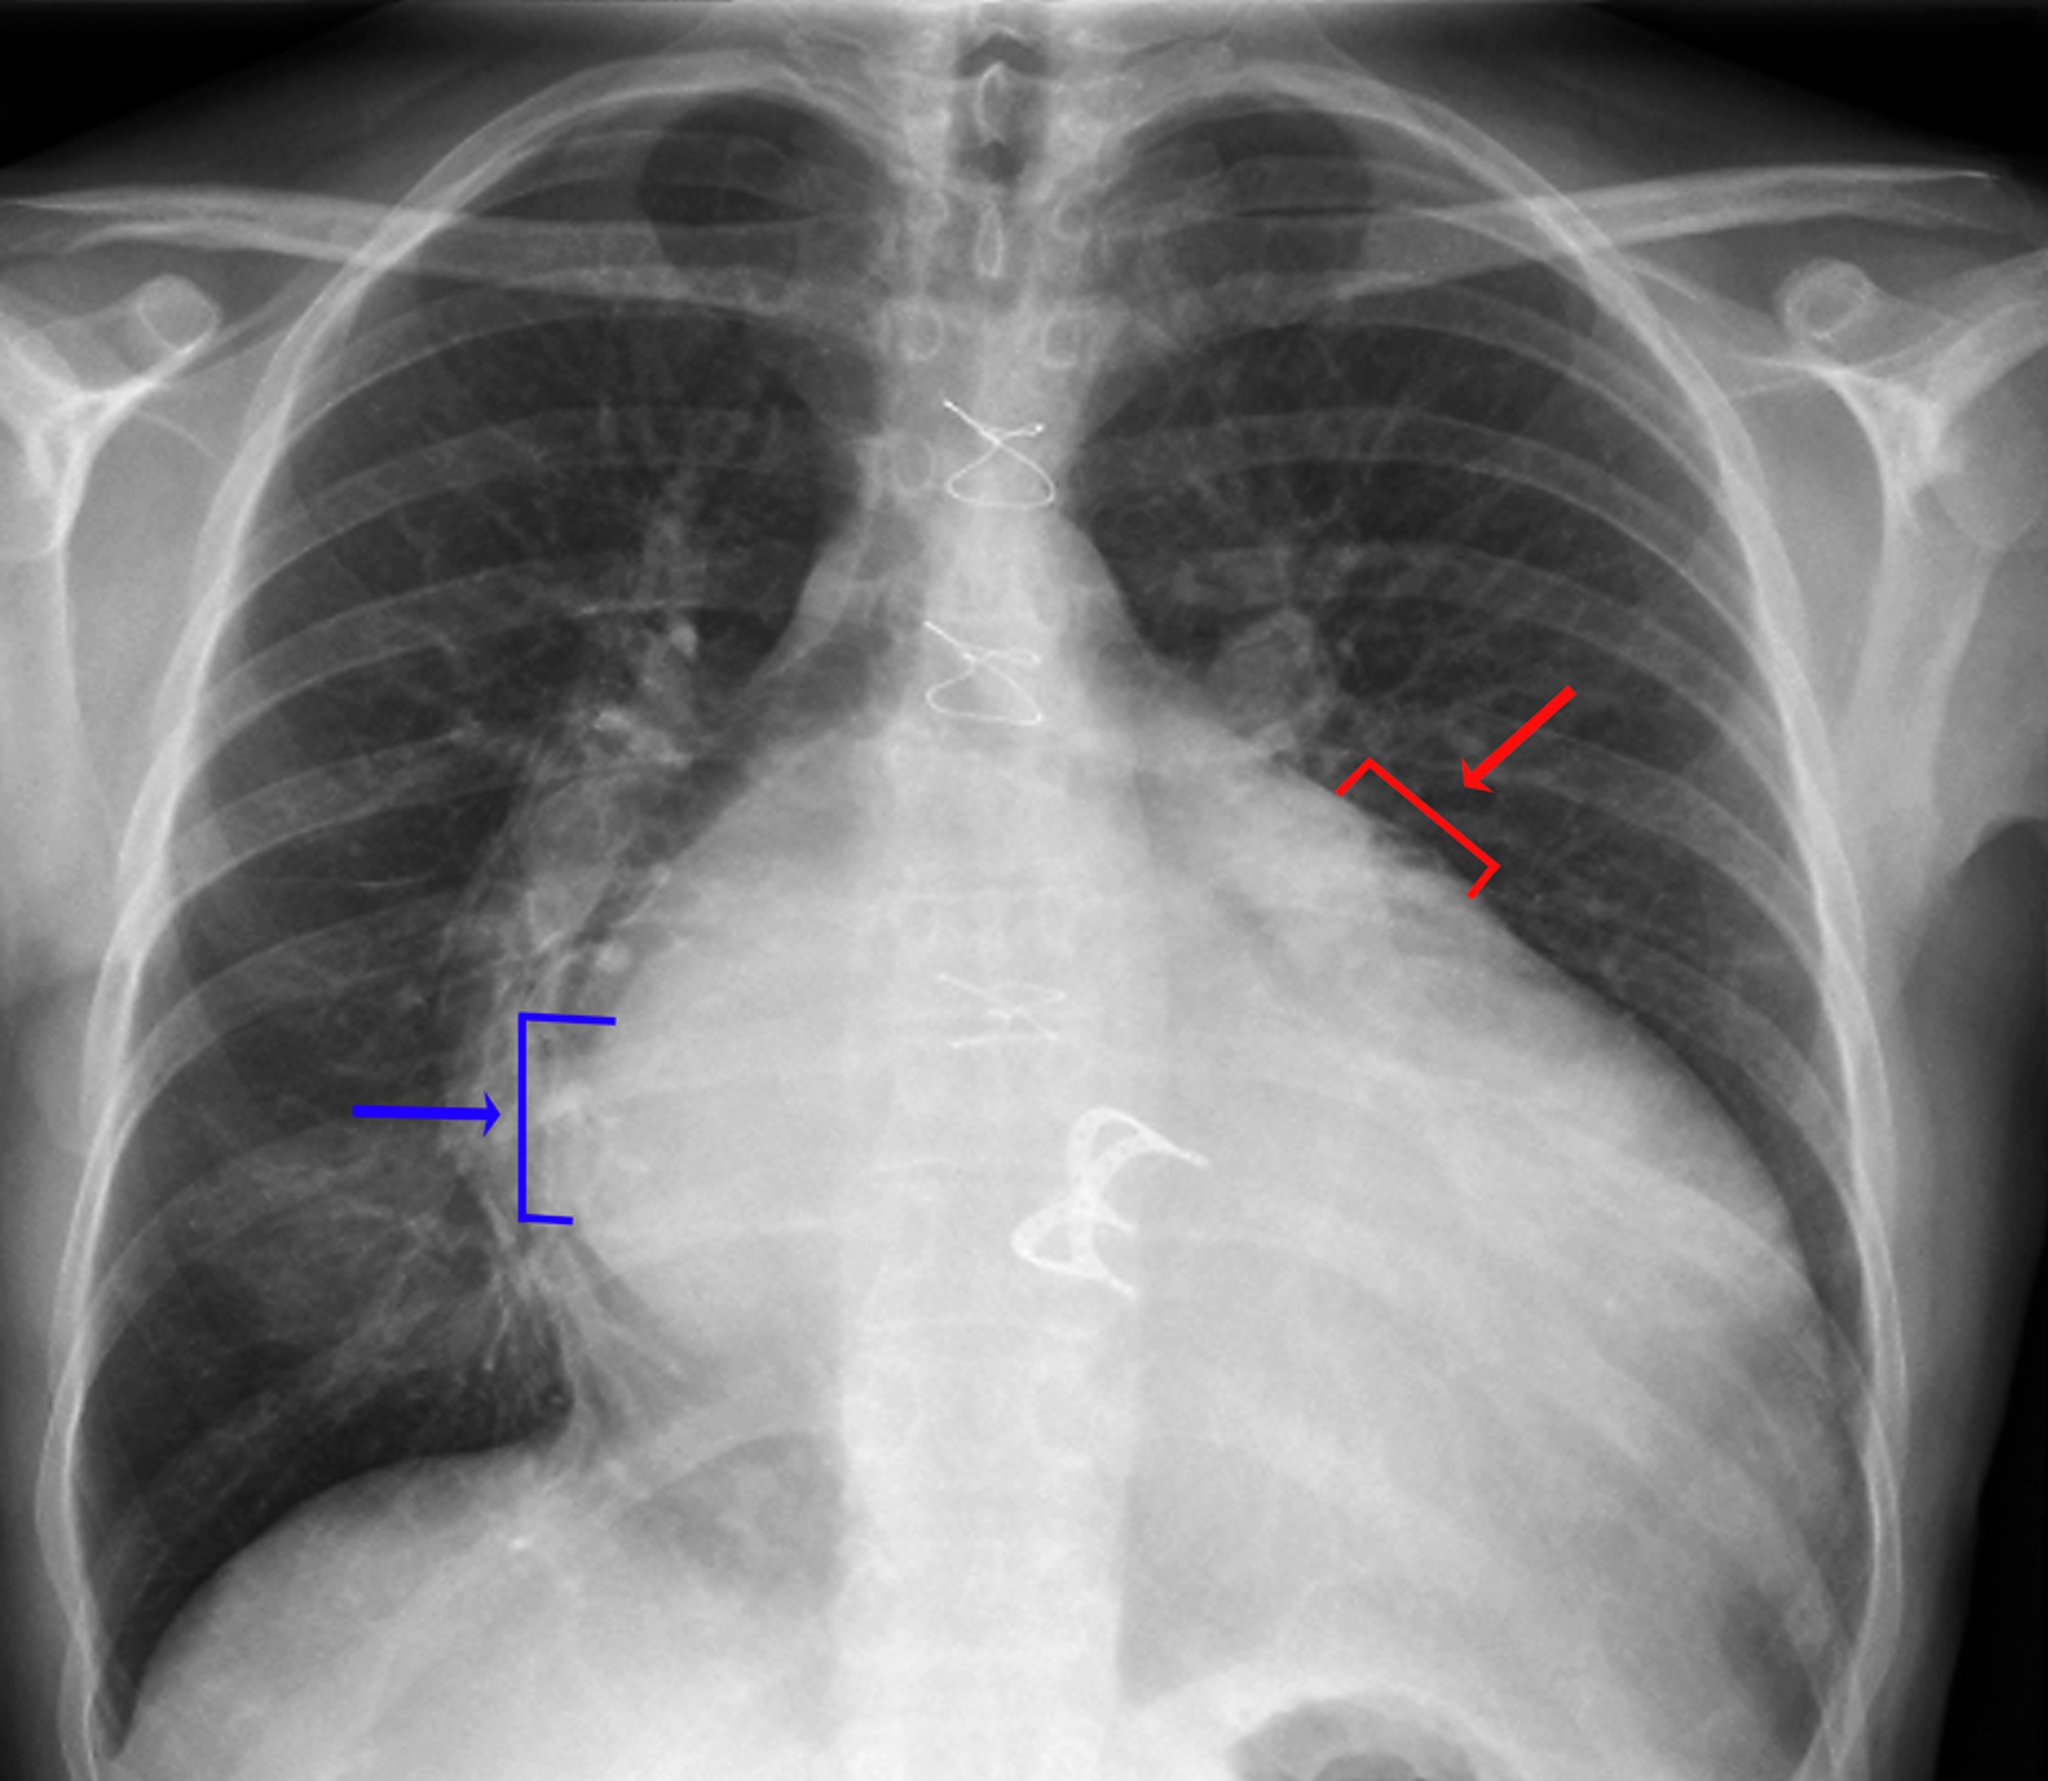

RX torace (protesi valvolare cardiaca)

I segni di aumento del volume atriale sinistro comprendono una densità visibile dell'atrio sinistro nell'emitorace destro (freccia blu, segno della doppia densità), una maggiore (> 7 cm) distanza tra il bordo atriale sinistro nell'emitorace destro e il bronco principale sinistro, una convessità lungo il margine superiore sinistro del cuore causata da un ingrossamento dell'auricola sinistra (freccia rossa), e un allargamento della carena con un'aumentata separazione tra i bronchi principali destro e sinistro. I segni di ingrandimento del ventricolo sinistro comprendono un ingrandimento della silhouette cardiaca e uno spostamento del margine verso la sinistra e il basso del margine sinistro del cuore.